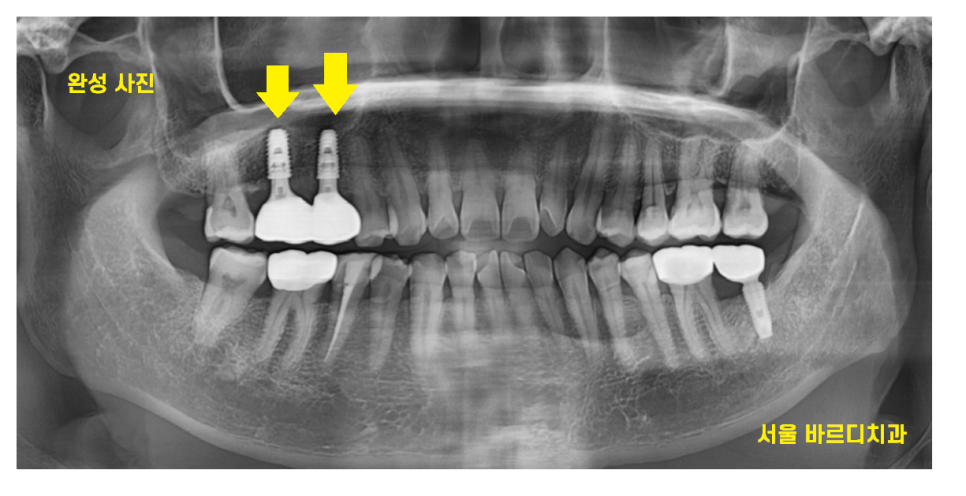

24.01.02

고덕동 임플란트 수술 후 약 4개월 뒤

보철을 올려드렸습니다.

발치하고 6개월

수술하고 4개월

10개월정도 걸렸네요.

두개의 임플란트를 묶어

튼튼하게 만들어드렸습니다.